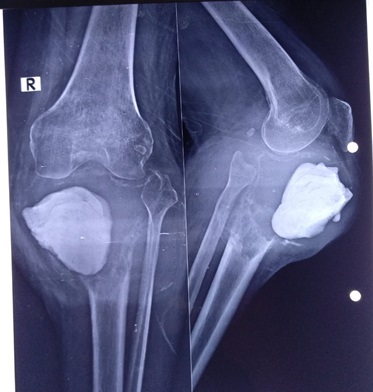

Children and adults with tumors and tumor-like disorders of the bone and soft tissue, such as bone metastases, sarcomas, benign and malignant tumors of the bone or soft tissue, and pathologic fractures, are treated by the Division of Orthopaedic Oncology, which provides them with the highest quality care.

Orthopedic oncology, also known as Musculoskeletal Oncology, focuses on the diagnosis and treatment of both benign and malignant bone tumors, along with other unusual lesions affecting the musculoskeletal system. Bone cancer and soft tissue sarcomas, though rare, demand a comprehensive, multidisciplinary approach to diagnosis and treatment.